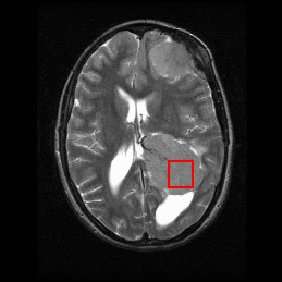

Shown below is an MRI brain scan (in the axial plane, that is slicing from front-to-back and side-to-side through the head) showing a brain tumor (meningioma) at the bottom right. The red box shows the volume of interest from which chemical information was obtained by MRS (a cube with 2 cm sides which produces a square when intersecting the 5 mm thick slice of the MRI scan).